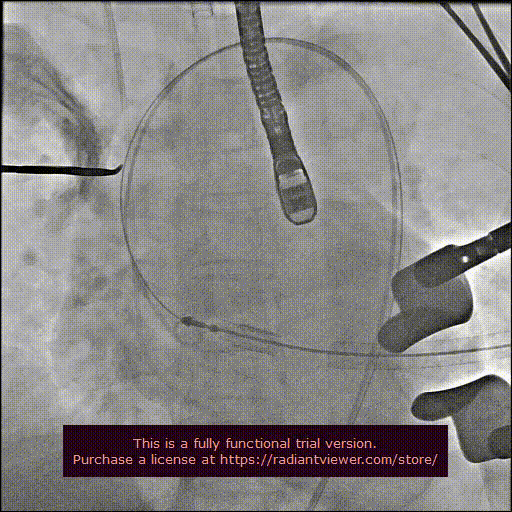

造影显示主动脉窦部

从心尖置入输送系统

定位件入窦

瓣膜降至瓣环平面

释放瓣膜

造影确认瓣膜位置

撤出输送系统

造影确认植入效果